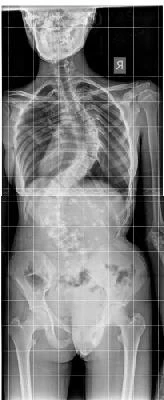

• علاج انحراف العمود الفقري

تحياتي لك..أختي لديها انحراف شديد في العمود الفقري في منطقة الكتف ولديها أيضًا قرص الخصر..أرسل لك الصور والشريط العصبي والعضلات..أريد أن أطلب رأيك في الطريقة التي يعاملون بها وما رأيك هو أفضل طريقة لعلاجه لأنهم مؤلمون للغاية الآن لدرجة أنهم لا يستطيعون القيام بأي تمرين ، وأيضًا الجلوس والوقوف والوقوف..لأنه سيكون حاملًا ، وبهذه المشاكل من غير المرجح أن نفعل ذلك..شكرا جزيلا لك..

مرحبًا ، هناك kyphosus شديد وإذا كان من الأفضل التحقق من ذلك..

مع عرض خدمتك. الدكتور.عانى أختي من العمود الفقري الشديد في منطقة الكتف وكذلك القرص القطني.أرسل الصور والخبراء إلى العصب والعضلات.أريد أن أرى رأيك في طريقة علاج علاجك، وفي رأيك، إنها أفضل طريقة لمعاملتها، لأن لديها الآن الكثير من الألم الذي لا يمكن القيام به من قبل أي رياضة ويجلس في الجلوس والوقوف والوقوف الكثير من الألم..لأنه يعتزم أن يكون حاملا، ومع هذه المشاكل، من غير المرجح أن نجعل هذا؟.شكرا جزيلا لشكركم.

مرحبا هو خلفي حاد، وفي حالة الألم تحقق بشكل أفضل.من المرجح أن تتطلب الجراحة التصحيحية.